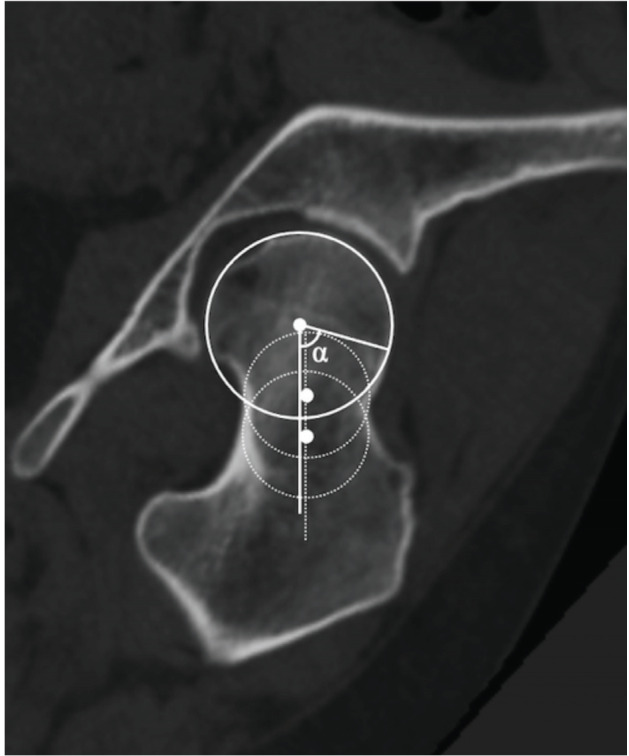

Materials and methods: This retrospective study included 57 patients with DDH (77 hips) who underwent PAO (DDH group). The control group comprised 30 patients (30 hips) with unilateral femoral head necrosis and contralateral unaffected hips (healthy hips). Coronal planes were created parallel to the femoral neck axis based on three-dimensional image analysis of hip computed tomography images. Coronal slices were obtained using clockwise rotation around the femoral neck axis in 15° increments, creating seven positions for measuring alpha (α)-angles. The superior and anterior directions were defined as 12 o'clock and 3 o'clock, respectively. Cam deformity was defined as an α-angle ≥60°. Outcome measurements were the α-angles of seven slices, cam deformity, and correlations between the maximum value of the α-angles and related factors.